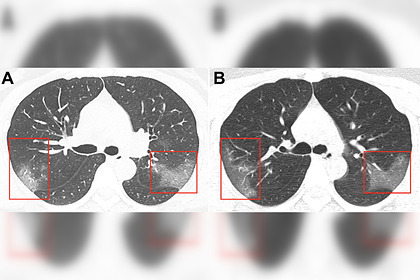

عرض الأطباء الصينيون صورا لرئتي مصاب بفيروس كورونا 2019-nCoV لمريضة تبلغ من العمر 33 عاما.

وعلى أساس الخصائص الوبائية والأعراض السريرية ونتائج التصوير الطبقي المحوري، تم تشخيص إصابتها بالالتهاب الرئوي 2019-nCoV.

وبعد ثلاثة أيام من العلاج، اتسعت رقعة المنطقة المصابة من الرئتين (الصورة ب) - في الصور تبدو معتمة.